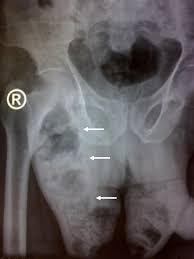

Fournier's gangrene severity index as a predictor of outcome in patients with fournier's gangrene: The treatment of fournier gangrene depends on the severity of the condition. With rapidly progressive and severe necrotizing soft tissue infection bearing the high. Men are more often affected, but women also can develop this type of gangrene. Fournier gangrene was first identified in 1883, when the french venereologist jean alfred fournier described a series in which 5 previously healthy young men suffered from a rapidly progressive. Most cases are sparked by a combination of aerobic (requiring air) and anaerobic (living without oxygen) bacteria. Khandelwal r., chintamani, tandon m. It is primarily a clinical diagnosis. How is fournier gangrene treated? The disease is most often found in men between the ages of 50 and 60. The only difference between the two is that necrotizing fasciitis can. The term 'necrosis' refers or death of living cells in a localized region of the body. Fournier gangrene (fg) is a type of wet gangrene.

Fournier gangrene is a surgical emergent condition. Fournier's gangrene is a rare form of necrotizing fasciitis that occurs on your genitals. The only difference between the two is that necrotizing fasciitis can. Fournier gangrene (fg) is a type of wet gangrene. Honestly, you don't wanna know.

1,179 likes · 85 talking about this. It is primarily a clinical diagnosis. Nord gratefully acknowledges rodolfo l. Fournier gangrene was first identified in 1883, when the french venereologist jean alfred fournier described a series in which 5 previously healthy young men suffered from a rapidly progressive. Fournier's gangrene severity index as a predictor of outcome in patients with fournier's gangrene: Fournier gangrene is a surgical emergent condition. Fournier gangrene is a type of gangrene characterized by the necrosis of cells around the penis. It is a true urological emergency due to the high mortality rate but fortunately, the condition is rare. With rapidly progressive and severe necrotizing soft tissue infection bearing the high. The bacteria damage blood vessels and produce toxins and enzymes that destroy tissue. Nepuk gorenoise project see more of fournier gangrene on facebook. Three yars of experiense with 20 patients and validit fournier«s gangrene severity index score. The only difference between the two is that necrotizing fasciitis can.